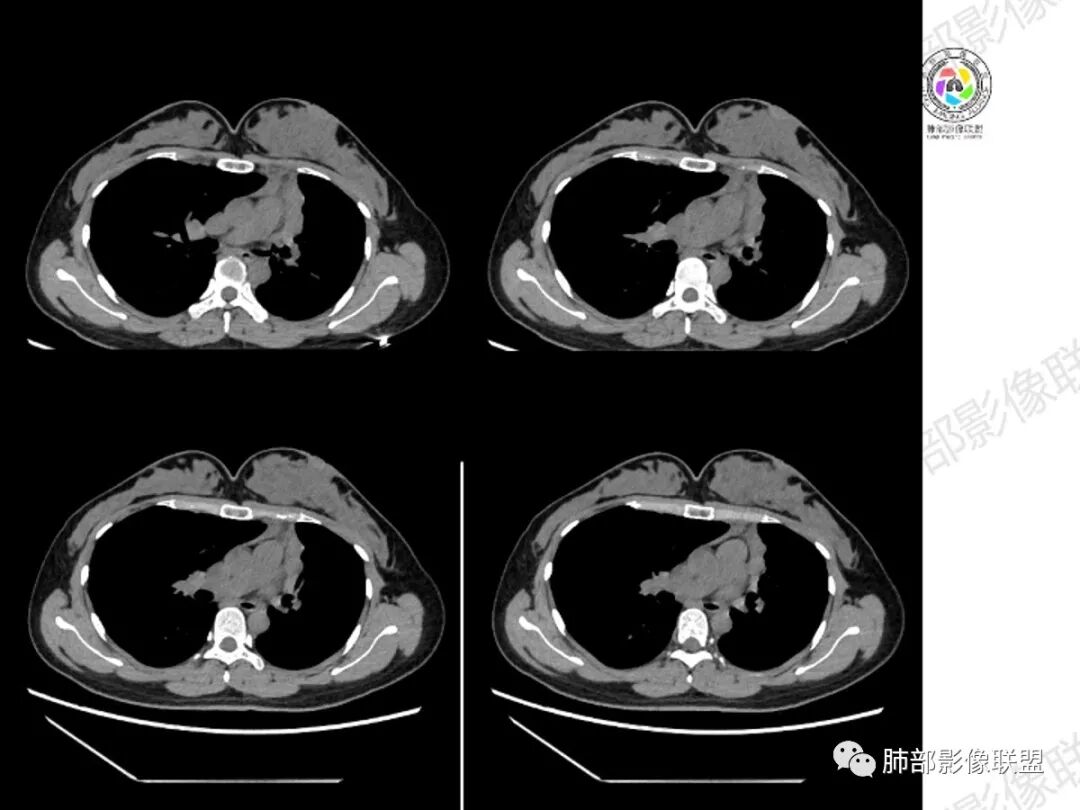

影像:左肺上叶支气管黏液栓伴实变不张,实变区域强化明显,小钙化灶,左肺下叶散在结节

左肺上叶纵膈旁实变影,边缘清晰,密度不均,可见斑点状钙化及条形低密度粘液栓,与纵膈胸膜脂肪间隙清晰,实性成分强化明显,周围肺组织内见多发小结节状卫星灶,左肺上叶体积缩小,年轻女性,考虑:结核,鉴别:粘液表皮样癌

年轻女性,慢性病程,左上叶纵隔旁大片实变,心脏纵隔左移,左主及左上叶支气管变窄呈针孔样,实变内可见斑点状钙化,显著不均匀强化,内可见低密度粘液拴,显著强化不支持TB,左上叶不张在腺癌少见,综合病变部位及强化表现考虑粘液表皮样癌,其次考虑类癌

年轻女性,左肺上叶纵膈旁实变影,边界尚可,密度不均,内部可见斑点状钙化及条形低密度粘液栓,增强实性成分强化明显,周围肺组织内可见多发小结节状卫星灶,左肺上叶体积缩小,首先考虑肉芽肿性病变,结核可能,鉴别:粘液表皮样癌。

女性,29岁,咳嗽咳痰,痰中带血1月余,CT示左肺尖胸膜下纵隔旁不规则实变影,内部可见小点状钙化灶,支气管略狭窄,增强可见低密度不强化区,粘液栓?实性成分明显不均匀强化,局部与左肺动脉分界不清,另左肺可见多发小结节,考虑为恶性,黏表可能,鉴别结核

年轻女性,咳嗦咳痰伴咳血1月多,ct可见纵隔左移,左肺容积减小,左肺上叶可见一不规则实变影,朝肺内侧边界清楚,部分边缘与纵隔界限模糊,临近支气管堵塞,内见点状钙化,增强不均匀强化,内可见多个低密度区,粘液?并与左肺动脉界限模糊,似受侵,考虑恶性,黏表?但病灶远端有多发小结节,卫星灶?结核待排

胸部CT:左肺体积缩小,左肺上叶前段纵隔旁胸膜下大片实变影,边缘清楚、匀齐、平直收缩,部分略膨隆,周围多发结节、树芽卫星灶,纵隔窗病灶与纵隔胸膜黏连,实变内多发点状钙化。平扫密度尚均匀,增强扫描不均匀明显强化,多个低密度区,呈仙人掌样,伴有条状血管影,考虑慢性炎症伴左上叶前段支气管闭塞,TB?鉴别黏表、腺癌等。